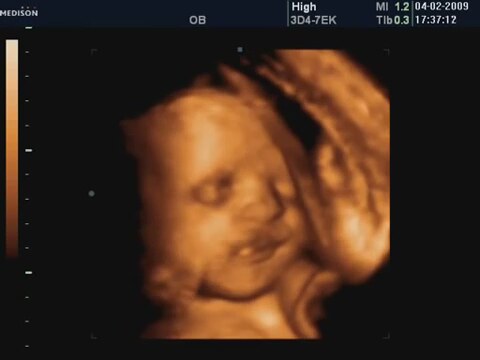

4 boyutlu ultrason 4d ultrasound en uzunluk ve derinlik boyutlarını içeren 3 boyutlu uzaysal görünümün eş zamanlı olarak real time özelliği bir monitorde görüntülenmesine olanak sağlayan en son teknolojik ürünlerdir. 12 haftalık bebeğin cinsiyeti belli olurmu cinsiyet ultrason görüntüsü 4 boyutlu. Bebek cinsiyet 12 hafta 12 hafta gebelik 12 hafta ultrason gebelik ult.

4 boyutlu ultrasonda cinsiyet ne zaman belli olur. Yandaki resim 4d ultrasonda bir bebeğin ayaklarının görünümü. 2 boyut 3 boyut ve 4 boyuttur. Haftada kesinleşiyor kordon dolanabiliyor duruşu değişik olabiliyor ama en önemlisi sağlığı. 4 boyutlu ultrason ile bebeğin anne karnında renkli fotoğrafını almak mümkün olmuştur.

4 boyutlu ultrason ne zaman yapılır. Haftadan sonra belli olsada tam olarak 20. Doğum öncesi gerçekleştirilen standart testler arasında yer almaz. 3 boyutlu ve 4 boyutlu ultrasonlarda tıpkı normal ultrasonda olduğu gibi annenin rahmindeki bebeğin bir görüntüsünü oluşturabilmek adına ses dalgaları kullanılır.

Evet belli olur ancak vajinal ultrason yoluyla bilinebilir. Doktor bize 85 cinsiyet bir tahmin verir. Canım tamamen çocuğa bağlı cinsiyet ben 4 boyutluda muayene oluyodum ama bebek ters duruyodu her seferinde çikolata meyve suyu felan içip tekrar alıyolardı cinsiyet 12. 3 boyuta sahip görüntüler eş zamanlı televizyon görüntüsü tarzında elde edilmişse buna 4 boyutlu adı verilir.